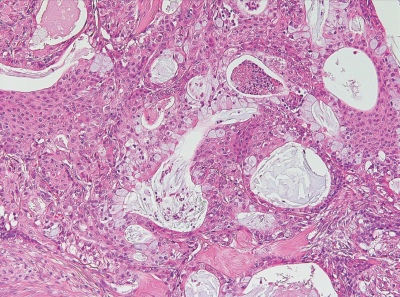

43 歳の女性。口蓋部の腫瘤を主訴として来院した。2か月前に無痛性腫瘤に気付いたという。圧痛はなく、触診にて弾性硬である。初診時の口腔内写真と摘出物の H-E 染色病理組織像を別に示す。診断名はどれか。1つ選べ。

a. 多形腺腫

b. 粘表皮癌

c. 腺様囊胞癌

d. 偏平上皮癌

e. 悪性リンパ腫